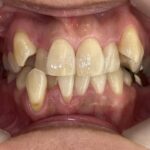

行ったご提案・治療内容

取り外し式のマウスピース矯正装置「インビザラインフル」で歯並びを改善する治療をご提案しました。

インビザラインフルで奥歯からしっかり動かすことで、歯を抜かずに治療できることを丁寧にご説明し、同意いただきました。

歯を動かす際は、歯並びの幅を拡大し、全ての歯がきれいに並ぶように治療計画を立てました。